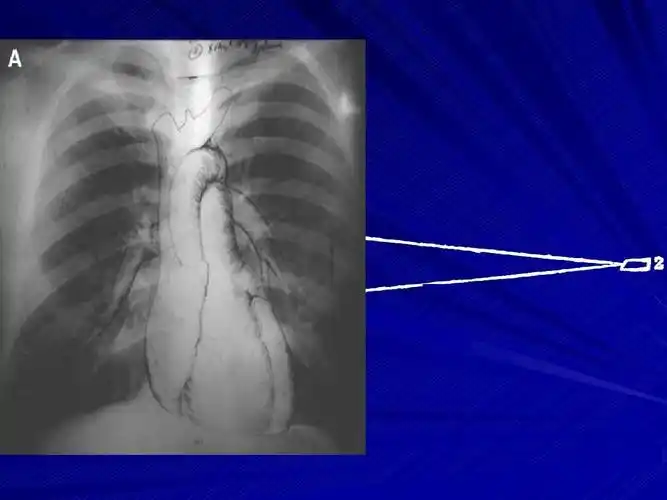

心脏测量及常见病弧线改变

诊断:二尖瓣 狭窄并关闭不全.

二尖瓣狭窄伴关闭不全(图1)